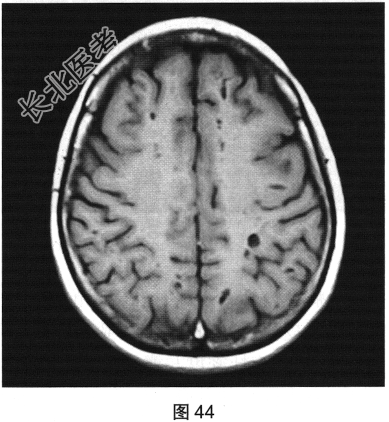

- [材料题] 患者女性,56岁,诉头痛、头晕多年,要求行颅脑MRI检查。查体:神志清楚,问答切题,查体合作。双眼睑无水肿、下垂及闭合不全,双侧瞳孔直径约3.0mm,直接、间接反射均灵敏。双眼视力视野粗侧无异常。发音清晰无嘶哑。耸肩及转头力量对称。四肢活动灵活,肌力、肌张力正常,深浅感觉基本正常;病理征阴性。患者行颅脑MRI检查,如图41~图44所示。

- 多项选择题1.根据患者MRI T1WI和T2WI图像,需要鉴别诊断的疾病有( )

- 多项选择题2.[提示]患者行FLAIR、DWI及增强扫描,见图45~图54。该患者MRI影像的主要阳性表现有( )

C、双侧放射冠及半卵圆中心多发条状、圆形及卵圆形异常信号灶

- 多项选择题3.根据患者MRI表现,本病最可能的诊断是( )

B、扩大血管周围间隙

- 多项选择题4.关于增大血管周围间隙,叙述正确的有( )

B、病灶在所有MRI序列上均有脑脊液信号相似

C、是与穿动脉伴行的含有间质液体的由柔脑膜细胞包绕的囊性结构,与蛛网膜下腔相通

F、血管周围间隙又称作Virchow-Robin(VR)间隙